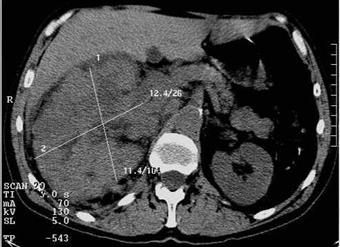

| Рис. 6.25. Компьютерная томограмма брюшной полости на уровне L2 позвонка. Правая почка значительно увеличена, контуры ее неровные, структура неоднородная. Почечно-клеточный рак правой почки. |